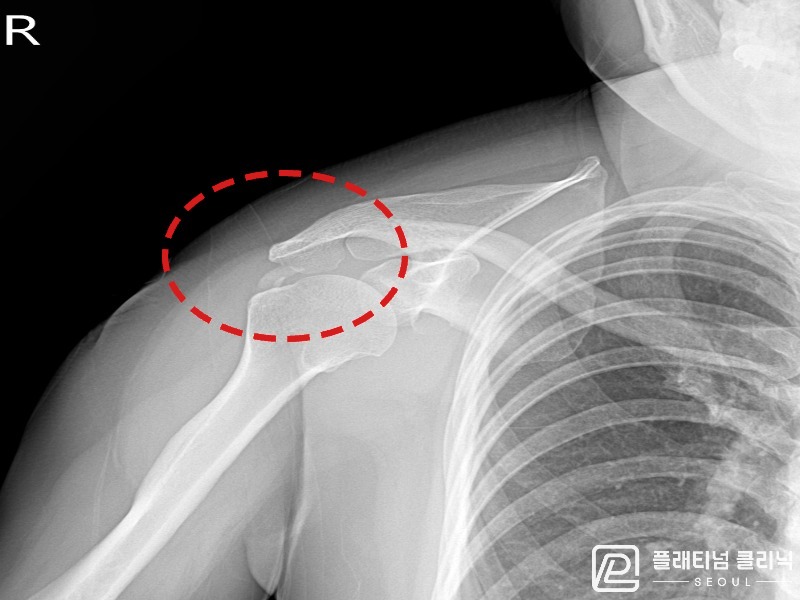

[촬영시기:21.10.21~21.10.30]

[석회분쇄흡입술] 우측 어깨 통증과 운동 제한으로 일상생활이 불편해진 30대 여성 환자로, X-ray에서 우측 극상근건 내 석회 침착이 확인되어 석회분쇄흡입술을 시행하였습니다.